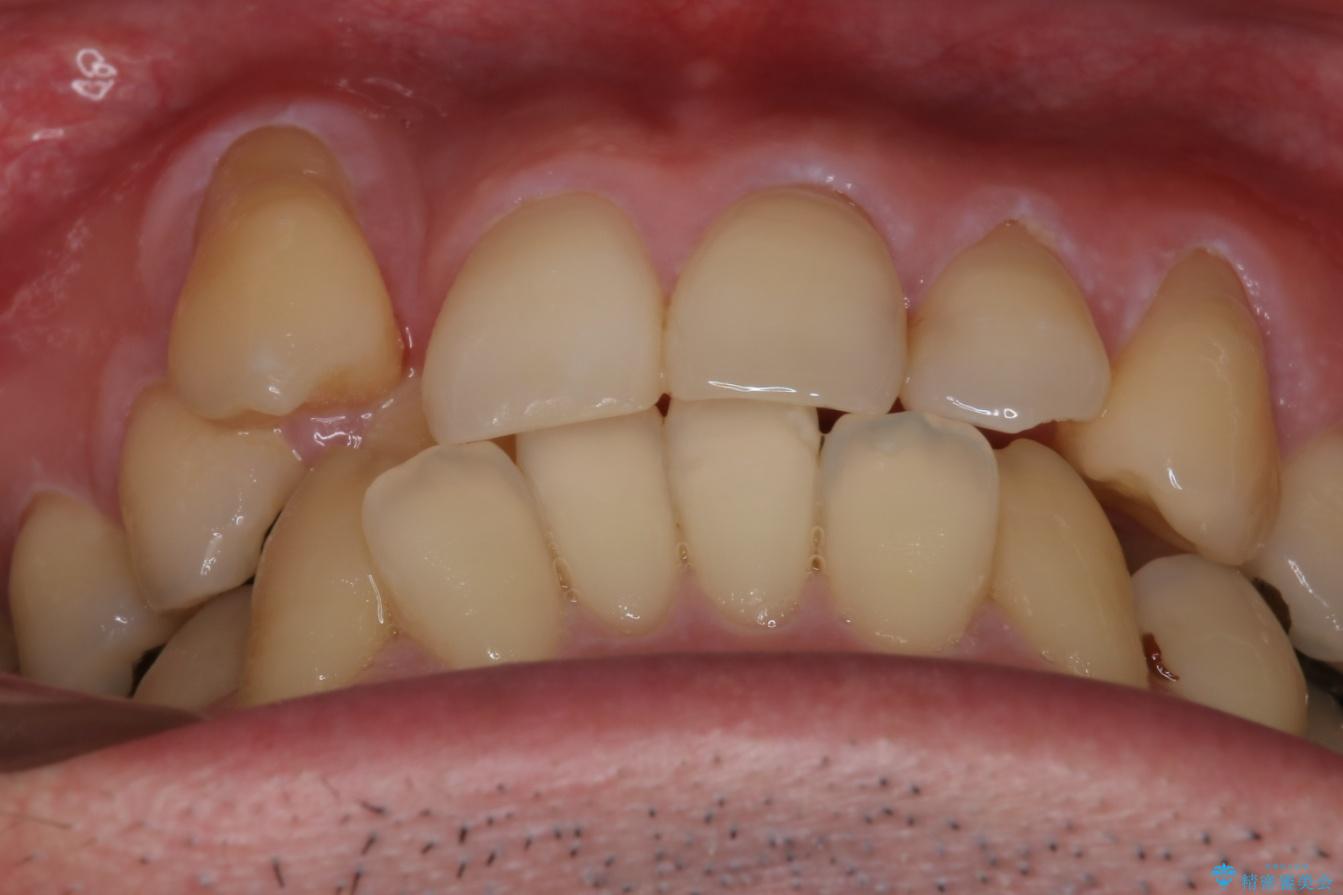

- 右上2番目の歯が舌側転位していることと前歯の叢生(がたつき)を主訴に来院されました。

右上の犬歯が初診時よりかなり歯根露出しており、矯正の力をかけるとさらに歯根露出するリスクがあるため、右上の2番目の歯を前に出すためにも

右上の犬歯を抜歯して歯並びを整える治療計画を立てました。